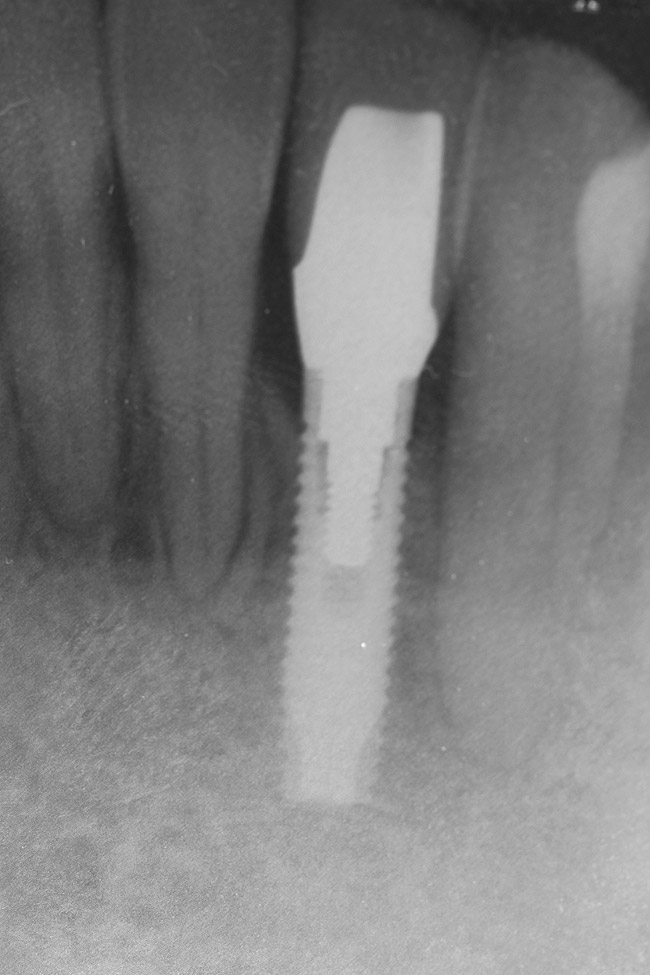

Figure 10  Radiograph of orthodontic distraction osteogenesis.

Figure 10

Figure 11  Radiograph showing developed implant site of tooth No. 23.

Figure 11

Following the first goal of orthodontia—moving tooth No. 22 to a proper functional and anatomical position—a periodontal reevaluation was performed, demonstrating an improvement in short- and long-term tooth prognosis. At this time, the decision was made to abort continual extrusion of teeth Nos. 21 and 22, although some attachment level discrepancy remained between Nos. 21 and 22 (Figure 14). Implant diagnostics ensued and included mounted study models and a diagnostic wax-up. A scanning appliance was created to demonstrate the desired prosthetic outcome requirements, and the patient was referred for computed tomography (CT) scans. CT scan assessment demonstrated successful orthodontically directed GBR to allow implant placement (Figure 15 through Figure 16). Only minor GBR therapy would be needed and could be accomplished simultaneously with implant installation. Guided implant placement occurred, using an open flap approach (Figure 17). During surgery, root dehiscences were noted on teeth Nos. 21, 22, 24, and 25, as well as the anticipated dehiscence following implant placement at No. 23 (Figure 18). A positioning reference (index) was secured after implant placement to facilitate a provisional prosthesis at stage II surgery. Cortical perforations then were placed adjacent to the implant to encourage angiogenesis (Figure 18), and mineralized freeze-dried bone allograft enhanced with platelet-derived growth factor was placed over the dehiscences for purposes of guided tissue regeneration and GBR (Figure 19). A highly resorbable collagen membrane was placed to stabilize the allograft. The flap was coronally repositioned, and primary-intention wound healing was achieved (Figure 20 and Figure 21). Following 4 months of stage I surgery, implant uncovery and immediate provisionalization were performed in conjunction with connective tissue grafting. Final orthodontic tooth movement then ensued, using the implant as anchorage to optimize end-tooth movements, interroot separation, and the cuspid-protected occlusal scheme. A final impression then was secured, and a zirconia abutment (Figure 22) with an all-ceramic restoration was fabricated for the prosthetic phase completion of No. 23 (Figure 23 through Figure 25).